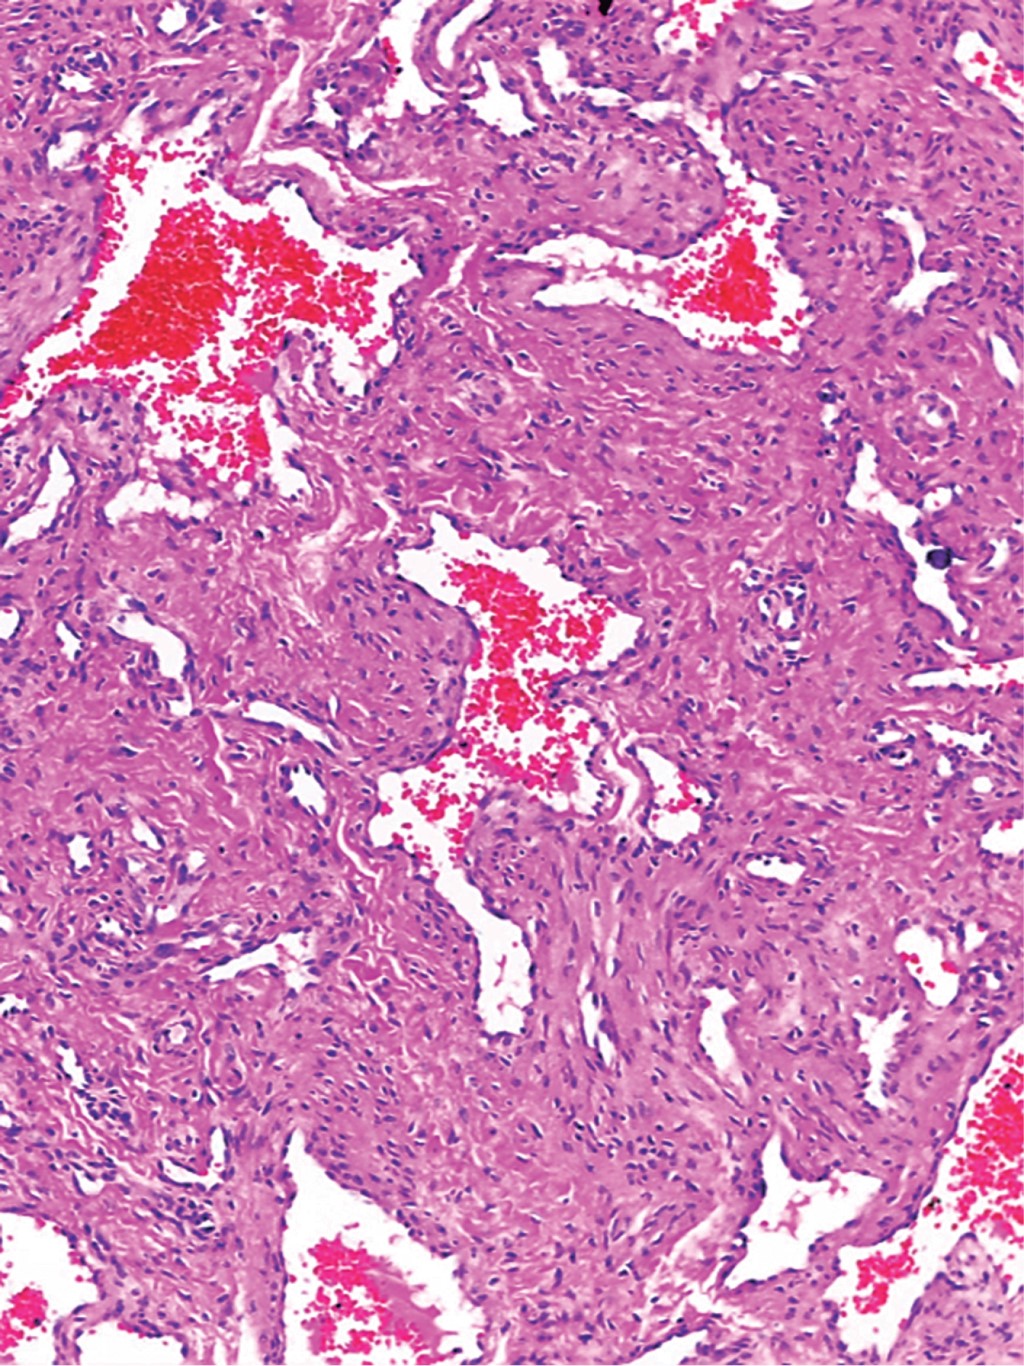

Se trata de un hombre de 69 años de edad, sin antecedentes de relevancia para el motivo de consulta, quien acude por presentar dermatosis localizada en cabeza, de la que afectaba pabellón auricular izquierdo a nivel de cara posterior del hélix, constituida por neoformación de 0.7 × 0.7 cm, hemiesférica, color azul-grisáceo, de superficie lisa, consistencia firme, bordes regulares, bien definidos; de dos años de evolución y sin síntomas asociados (Figura 1). A la dermatoscopía se observaron áreas azules sin estructura, con algunas zonas amarillentas y vasos lineales en la periferia (Figura 2). En el estudio histopatológico se observó epidermis con escasa capa córnea y tapones córneos. En la dermis superficial se observaron vasos dilatados rodeados por discretos infiltrados linfocitarios y zonas de edema entre las fibras de colágeno. En la dermis media y profunda se advierte la presencia de una neoformación circunscrita constituida por vasos dilatados y congestionados que se entremezclan con numerosas células fusiformes dispuestas en haces y que siguen diversos trayectos. La tinción tricrómica de Masson resultó positiva (Figuras 3, 4 y 5).

El abordaje diagnóstico puede incluir solicitar técnicas de imagen como el ultrasonido, que suele mostrar una masa ecogénica, homogénea, de bordes bien definidos y vascularizada.5,7 No obstante, estos hallazgos son inespecíficos y no permiten establecer el diagnóstico de forma certera, por lo que son necesarios la extirpación quirúrgica y el estudio histopatológico. Los hallazgos habituales con esta herramienta muestran una neoformación redonda, bien circunscrita, encapsulada, con haces de células musculares lisas entrelazadas y uniformes, distribuidas alrededor de vasos pequeños con paredes de calibre variable. Con frecuencia presentan degeneración mixoide, trombosis y calcificación distrófica.8 Con base en la morfología vascular, los angioleiomiomas pueden clasificarse en tres subtipos histopatológicos: sólido, venoso y cavernoso.9 En el venoso se observan vasos sanguíneos gruesos revestidos de músculo y haces de músculo liso intervascular.10 El sólido corresponde a 66% de los casos de angioleiomioma, seguido del venoso con 23% y el cavernoso con 11%.6

Figura 4